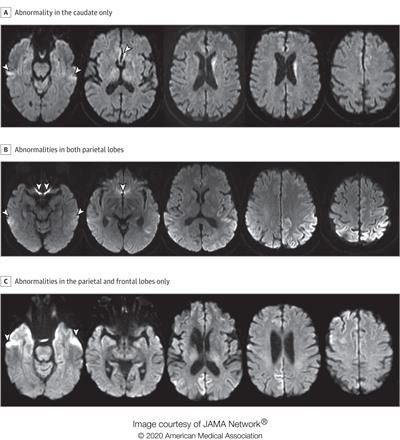

A: A man in his 70s with sCJD subtype VV2 with signal hyperintensity in the body of the left caudate, without evidence of signal abnormality in the putamina and neocortical ribbon. B: A woman in her 60s with sCJD subtype MM1 with signal hyperintensity in the cortical ribbon of both parietal lobes, left greater than right, and left precuneus without evidence of abnormality in the striatum, thalami, and cortical ribbon of the temporal and occipital lobes. C: A woman in her 70s with sCJD subtype MM1 with signal hyperintensity in the precuneus (right greater than left) and right parietal cortex. Images courtesy of JAMA Neurology.The study included diffusion MRI scans from 872 patients. Of these, 619 had sCJD, 102 had other prion diseases, and 151 had nonprion disease. Four radiologists scored the MRI scans of 200 patients randomly selected from the pool of 872; of the 200, 150 had sCJD and 50 had nonprion diseases.